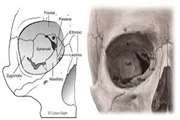

اندازه گیری حجم ،ابعاد و زوایای دیواره های اوربیت طبیعی با استفاده از سیتی اسکن اسپیرال اوربیت در افراد ایرانی مراجعه کننده به کلینیک اوربیت بیمارستان فارابی در فاصله زمانی سال 1401 تا 1403 1404/01/18 - 10:51